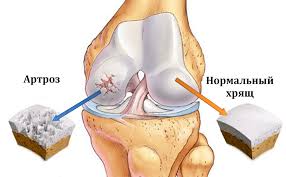

Колено - как шарнир между двух костей - бедренной кости верхней части ноги (бедро), и большеберцовой кости в нижней части ноги (голень). Обычно головки этих двух костей мягко скользят друг над другом внутри коленного сустава. Это возможно, потому что они покрыты суставным хрящом, гладкой и упругой тканью, которая покрывает и защищает головки костей, позволяя им двигаться друг над другом легко и безболезненно.

Показанием к эндопротезированию коленного сустава является остеоартрит. Вследствие данного заболевания коленный хрящ истончается, грубеет, а местами полностью истирается. Также на поверхности сустава могут образовываться костяные наросты, в результате кости "трутся" друг об друга, что вызывает боль, опухоль и ограничение подвижности в поражённом колене.